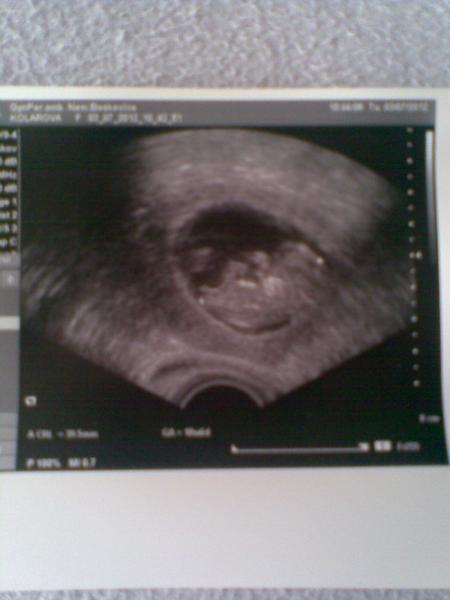

Holkyyyyy 🙂, tak mame dve srdicka 🙂, hlavicku, telicko a vse ok 🙂, ted jdu az 11.7. Uz do poradny k bilkove a v 30.7. Nt screen. 🙂